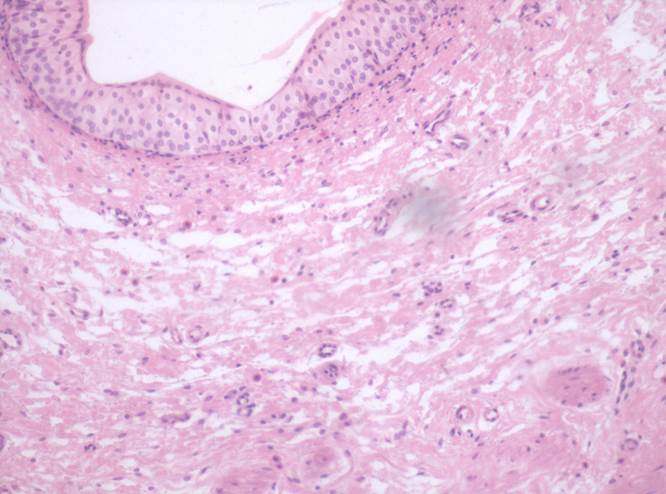

Препарат № 2. «Мочеточник», (окраска гематоксилином и эозином).

ОГП – 128

Слизистая оболочка:

1. переходный эпителий;

2. собственная пластинка.

II. Подслизистая оболочка.

III. Мышечная оболочка:

3. внутренний слой – продольный;

4. наружный слой – циркулярный.

IY. Адвентициальная оболочка.

5. рыхлая соединительная ткань

6. кровеносные сосуды